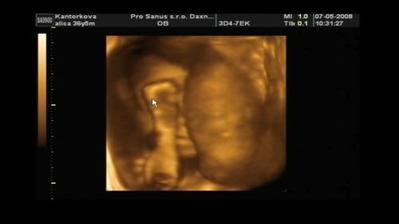

Naše druhé bábätko Filipko

V máji sme sa dozvedeli, že budeme mať druhého chlapčeka Samka alebo Filipka - stále sa nevieme rozhodnúť 🙂. Už sa ťa nevieme dočkať pokladík 🙂)

Náš druhý bubáčik sa narodil 8.septembra 2008 o 17:15 s mierami 50 cm a 3230 gramov